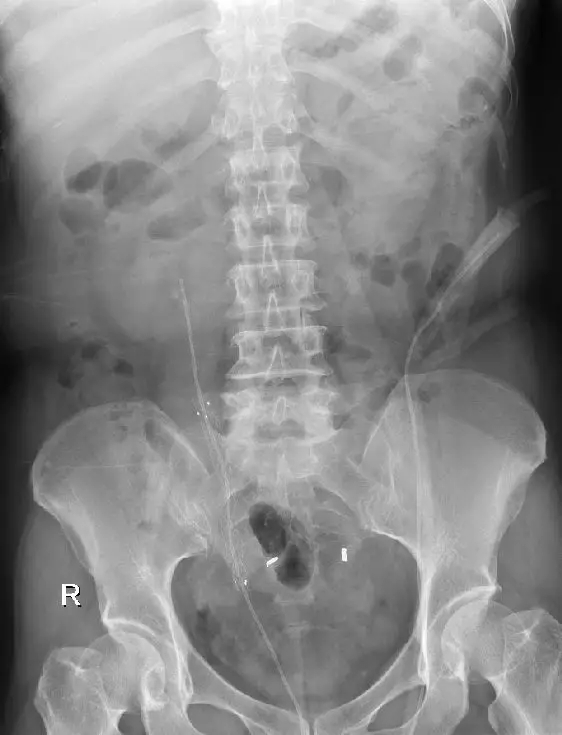

患者术前CT及静脉泌尿系造影资料

术后1月复查静脉泌尿系造影提示右肾功能良好。为彻底解决输尿管狭窄,避免狭窄复发,经科室讨论,认为输尿管狭窄与开放手术疤痕、反复输尿管结石梗阻、输尿管慢性炎症有关,留置常规输尿管内支架管治疗无效。决定Ⅱ期植入治疗输尿管狭窄的“黑科技”——ALLIUM输尿管支架。手术过程顺利,术后患者康复良好,术后3天顺利出院。

术后复查静脉泌尿系造影提示右肾恢复分泌功能术后提示成功植入Allium支架